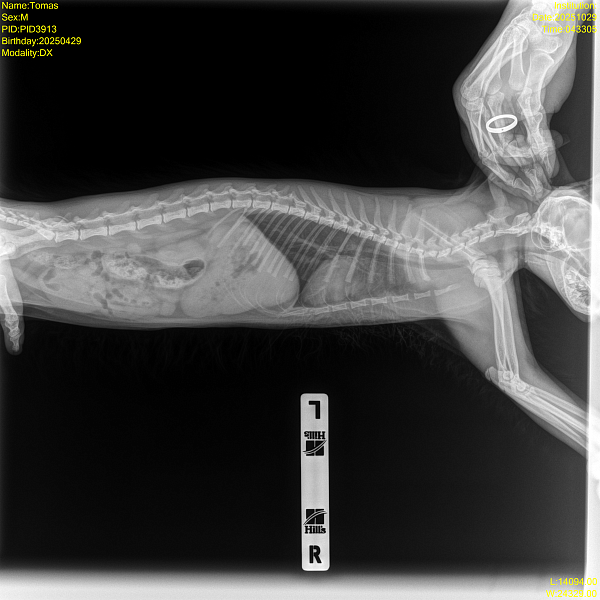

Рентген - смотрел кардиолог, сказал ничего патологического не видит, но может лучше показать пульмонологу для второго мнения.

Прикладываю заключение узи, рентген и видео.

Здравствуйте, дыхание с открытым ртом у кошек при активной физической активности и сильном беспокойстве это может быть вариантом нормы, а вот кашель нет. Наиболее частые причины кашля у кошек это бронхит и астма, дифференцировать эти состояния по рентгену невозможно. Если приступы кашля становятся частыми, то для уточнения диагноза назначают дополнительную диагностику - КТ грудной полости, бронхоальвеолярный лаваж. Если нет возможности провести такую диагностику, то начинаются эмпирическую терапию, чаще всего с ингаляций.

на Ваших снимках выраженных изменений в грудной полости нет, но нельзя исключать, что при сохранении симптомов особенно в виде кашля изменения появятся со временем, если речь идет о формирующейся хронической проблеме. Поэтому если кашель сохраняется, то снимок нужно повторять через 2-6 месяцев.